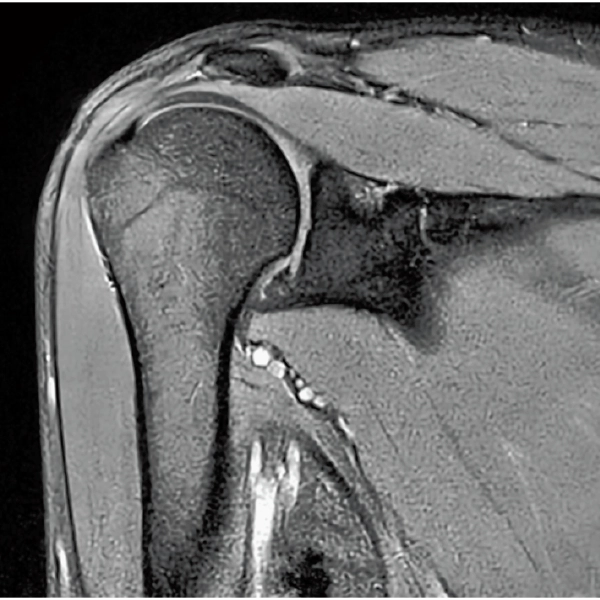

High Resolution

T2WI, 0.56×0.70×3.0mm, 2:28

T2*WI Multi Echo,

0.38×0.38×2.0mm

0.35×0.40×3.0mm, 2:55

3D Bone

0.93×0.93×1.2(0.6)mm

1.1×1.1×1.2(0.6)mm

3DisoFSE T2WI

0.75×0.75×1.1(0.55)mm